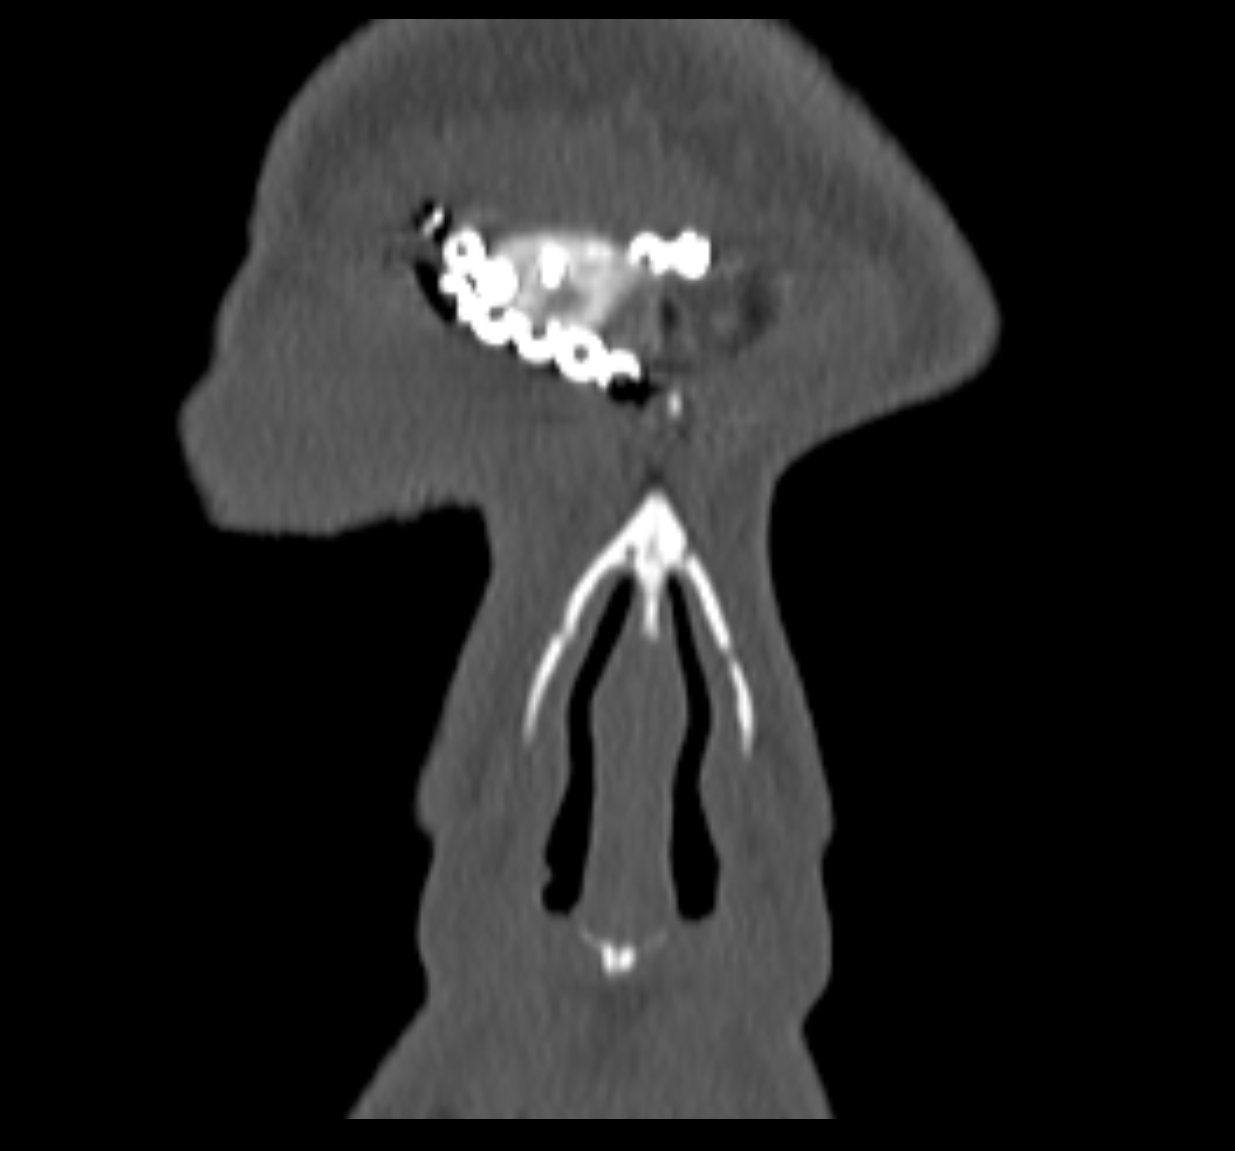

Ziua 1 postoperator, pacienta efectuează CT sinusuri paranazale de control care certifică ablația completă a formațiunii.